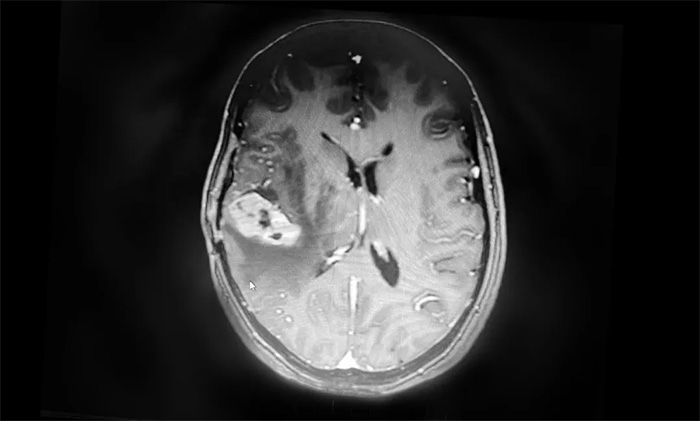

盧云鶴博士為患者進(jìn)一步完善檢查。MR檢查示右側(cè)顳葉內(nèi)見環(huán)片狀混雜信號(hào),大小約20mm*18mm,強(qiáng)化與水腫明顯。周圍腦溝、裂顯示欠清;右側(cè)側(cè)腦室受壓變形,中線結(jié)構(gòu)稍左偏,出現(xiàn)可疑腦膜轉(zhuǎn)移。

▲ MR示右側(cè)顳葉占位,占位效應(yīng)明顯

結(jié)合既往病史和影像學(xué)表現(xiàn),盧云鶴博士認(rèn)為,患者乳腺癌腦轉(zhuǎn)移瘤復(fù)發(fā)可能性較大。雖然占位本身體積不大,但其水腫帶已壓迫臨近腦室,患者出現(xiàn)頭痛頭暈癥狀,應(yīng)考慮采取合適的方法積極給予治療。